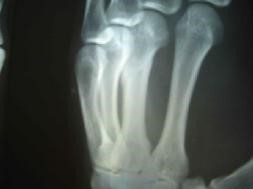

二零零五年六月在沈阳第一监狱拍的X光片子显示邢家秋左手中指骨折